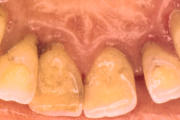

Krooniline parodontiit

Krooniline parodontiit on mikroobide poolt põhjustatud hammaste tugikudede põletik, mille tulemusena tekib progresseeruv alveolaarluu (nähtav röntgenograamil) ja periodontaalligamendi destruktsioon, igemetaskute moodustumine, igeme retsessioon või mõlemad kahjustused kombineeritult. Loe edasi »

- igemed veritsevad (19)

- igemed punetavad (21)

- igemed on tursunud/vohavad (17)

- puudulik suuhügieen (5)

- igemepealne hambakivi (5)

- igemealune hambakivi (4)